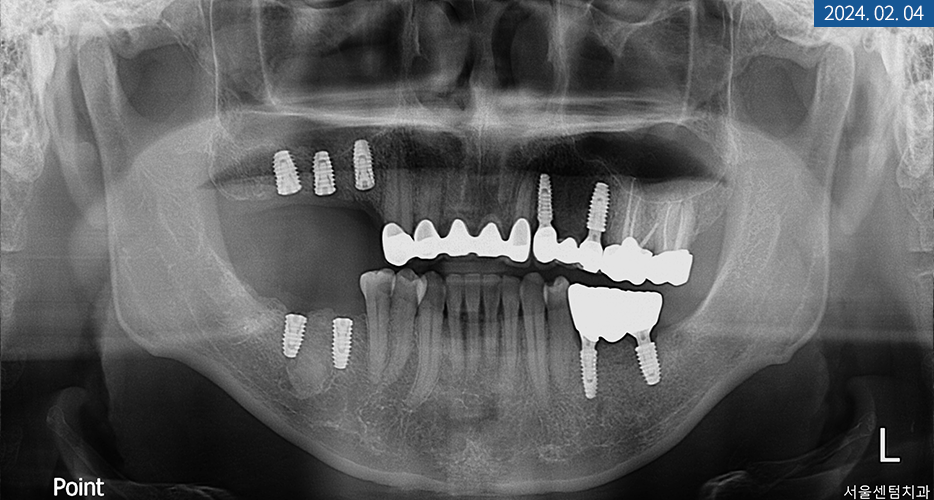

└ 첫 내원 당시 환자분의 잇몸과 치아 상태

위 사진의 상태를 갖고 계셨던

40대 남성분께서는 치아 상실이 돼서

저작 기능의 불편을 경험하고 계셨습니다.

파노라마 엑스레이를 찍어보니

상하악의 영구치가

전체적으로 많이 탈락돼있었습니다.

또한 좌측 상악 어금니에

치통과 더불어 염증 소견이 보여

신경 치료도 동반해야 했는데요.

환자분께서 음식을 어느 정도

씹을 수 있게 해달라고 하셨으며

경제적인 부분을 우려하셨기에

합리적인 방안으로 임플란트 브릿지를

식립하기로 했습니다.